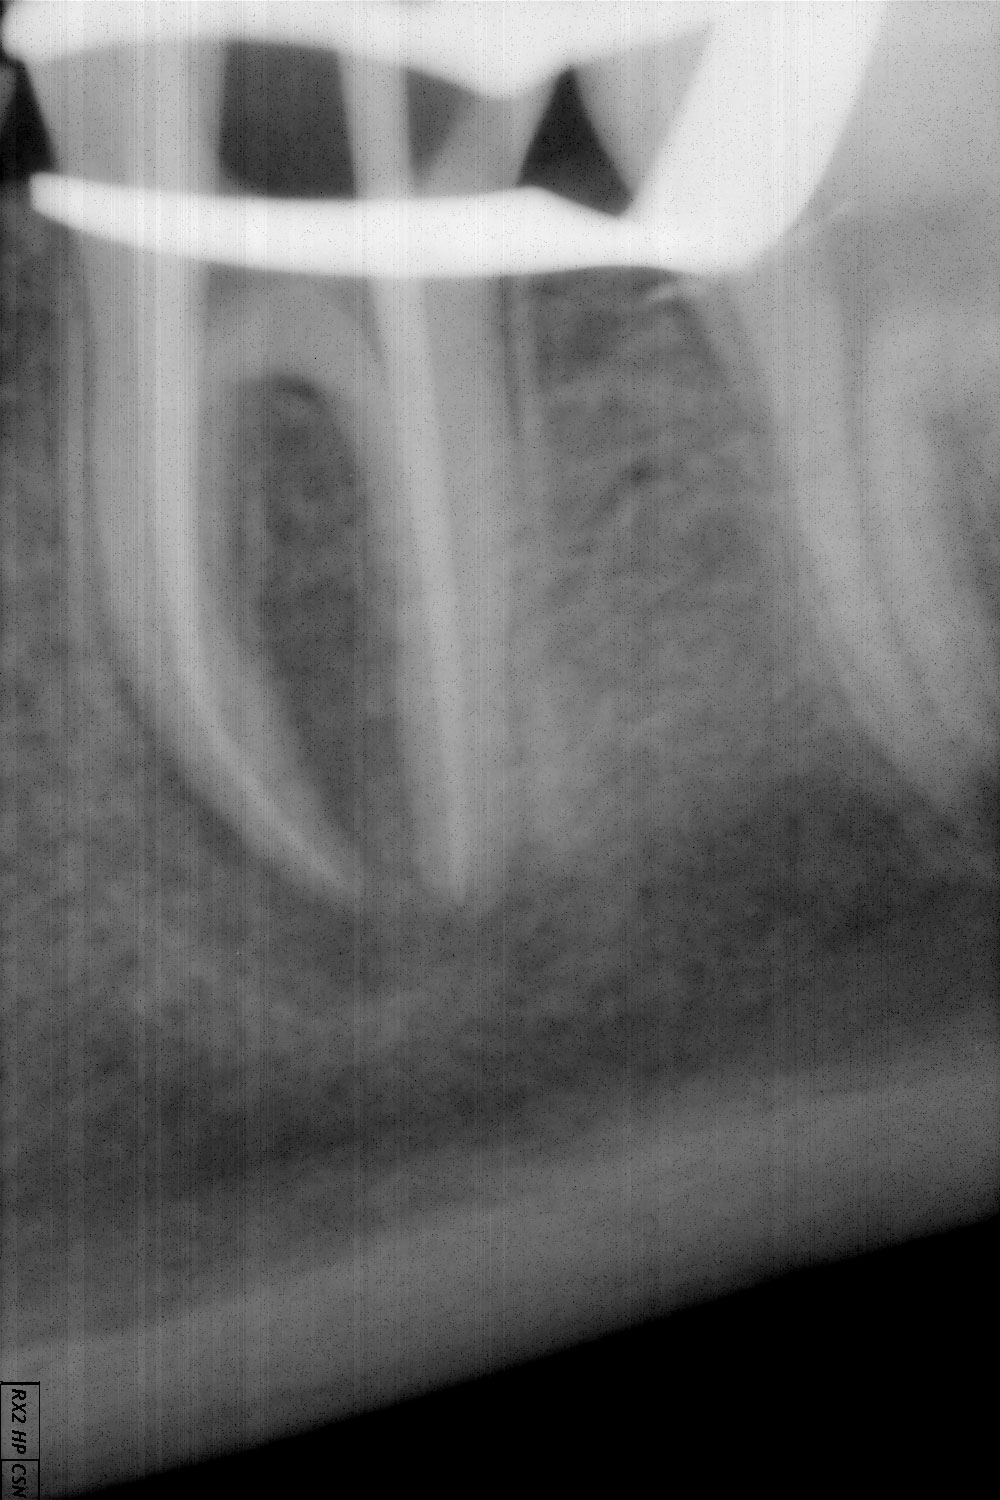

Pacientė kreipėsi dėl krūminio danties endodontinio gydymo. Pacientė skundėsi burnos ertmėje,  pažeisto danties projekcijoje, atsiradusia fistule („pūlinuku“). Dantis izoliuotas nuo seilių koferdamu, išvalyti karieso pažeisti audiniai, suformuota ertmė endodontiniam gydymui, kanalai išvalyti, taikyta kalcio hidroksido terapija. Išnykus fistulei , krūminio danties kanalai užplombuoti.

• Kanalai išvalyti, paruošti plombavimui, atlikta nuotrauka su plombine medžiaga